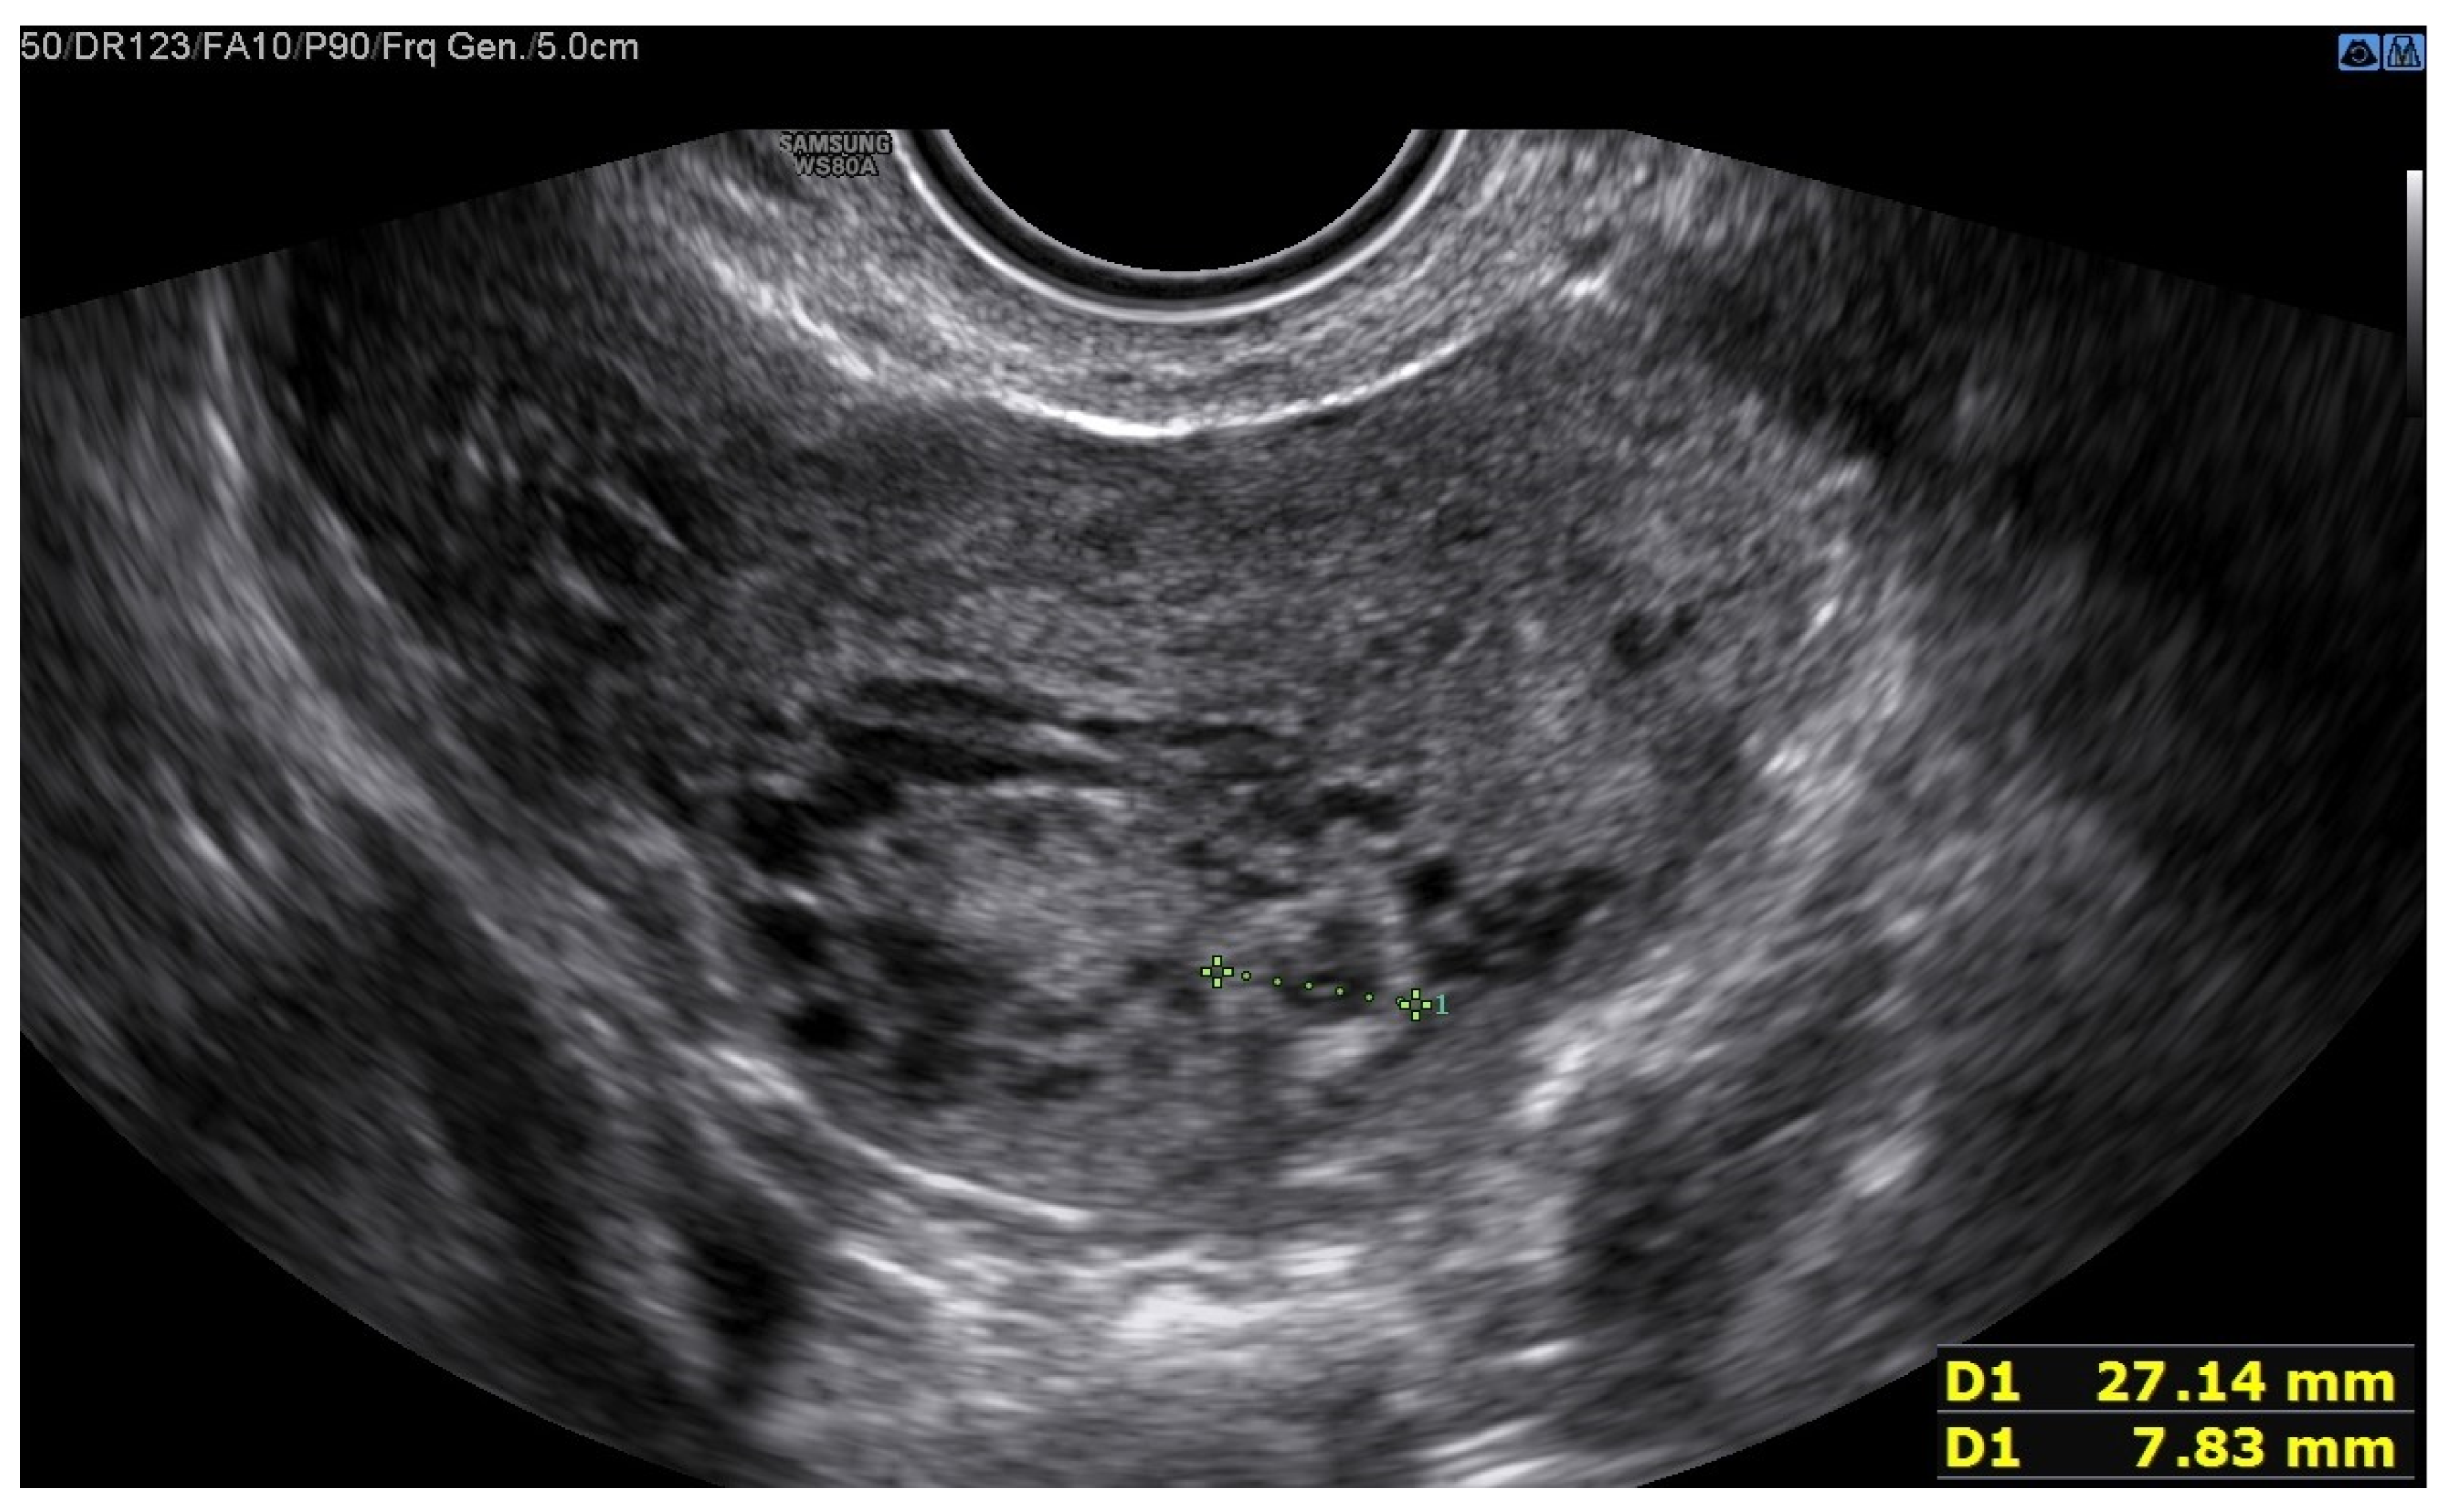

A 25-year-old woman, with a history of left tubal laparoscopic salpingectomy for an ectopic pregnancy, sought medical attention at the hospital’s emergency department after an episode of vaginal bleeding at 5 + 6 weeks of amenorrhea. At Day-1, her β-hCG was 2528 mUI/mL but a transvaginal ultrasound scan (TVUS) showed no clear evidence of pregnancy. Therefore, the patient was admitted with a diagnosis of pregnancy of unknown location (PUL). Upon admission, the patient was clinically and hemodynamically stable and did not report any pain or active bleeding. Serial measurement of her β-hCG in the following days was consistent with a suboptimal growth (3696 at Day-2, 5898 at Day-4, 10,984 at Day-7). Repeated TVUSs failed to show sure evidence of pregnancy until Day-7, when an intramural vascularized mass of 27 × 8 × 20 mm, with a gestational sac of 7 mm, a yolk sac and a 2 mm embryo with a heartbeat, was detected (Figure 1). Pelvic nuclear magnetic resonance (NMR) performed at Day-7 confirmed the presence of an intramyometrial T2-hypointense signal alteration of 20 mm in the right cornual area, surrounded by ectasic vessels, suggestive of interstitial pregnancy (Figure 2). After thorough counselling, a conservative management was proposed and accepted by the patient. The patient was administered a single oral dose of mifepristone 600 mg in combination with multidose systemic MTX 72 mg on days 0, 2, 4 and 6 from diagnosis. Follow-up by TVUS and β-hCG measurement was carried out. By Day-15, β-hCG reached a plateau and started reducing. A TVUS confirmed the termination of the pregnancy by involution of the gestational sac and the presence of the embryo with the disappearance of the fetal heartbeat. After 22 days from treatment, while the pregnancy was disappearing, in the same site, TVUS showed the appearance of a myometrial tubular hypoechoic region of 37 × 38 mm with an intensely vascular and multidirectional flow. Spectral Doppler ultrasound showed a low-resistance, high-velocity (peak systolic velocity of 128 cm/s) flow pattern, suggestive of uterine arteriovenous malformation (AVM) in the location of the previous interstitial pregnancy (Figure 3). The patient remained asymptomatic. To avoid menstrual bleeding and minimize the risk of metrorrhagia, a depot 3.75 mg shot of a GnRH analogue was administered every 28 days for 4 months. Considering the desire to preserve the fertility of the patient, the absence of guidelines for the treatment of AVM and the good results presented in the literature on uterine artery embolization as a conservative treatment, we performed a right uterine artery embolization, with sonographic resolution of the AVM within 3 months (Figure 4). We accessed the right common femoral artery and a 5-Fr introducing an angiographic sheath was placed. A 5-Fr Cobra catheter (Cook, Bloomington, IN, USA) was used to perform nonselective angiograms of the internal iliac arteries in order to achieve a general understanding of the vascular anatomy; the right internal iliac artery was selected after creating a Waltman loop with the Cobra catheter. The right uterine artery was selected using a microcatheter ranging from 2.0 to 2.4 Fr. As embolic materials, polyvinyl alcohol particles were used (Contour; Boston Scientific, Cork, Ireland). The rescue treatment had no complications. We present an unpublished case of interstitial pregnancy in a hemodynamically stable woman at an early gestational age successfully treated with medical therapy using MTX and mifepristone, who developed a peculiar complication.

Figure 1. The green line identifies the gestational sac and a 2 mm embryo without a heartbeat.